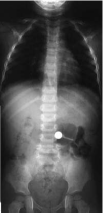

Refer to caption

Figure 3: An intersection of the 3d-test image.

In the case of a three-dimensional image, Fig. 4, the corresponding histogram, obtained by using the above method is shown in Fig. 4. One observes a higher asymmetry of the distribution of the projections in this case, compared to the same distribution of two-dimensional images, but qualitatively it is of the same type.

Further we investigate how the algorithm works in 3D. As noticed in the previous section, the distribution of the projection is similar, but more irregular and asymmetric.

Comparing the quality of the method on two and three-dimensional images, (Fig. 7), one can say that when the structure is clearly three dimensional, the algorithm working in 3D separates this structure much better than working in 2D section. The irrelevance of the dimension for the algorithm is probably the main advantage with respect to other algorithms, as for example the Hough transform [4]. The maximum execution time scales with N𝑁N as the number of pixels MNdlog2Nd𝑀superscript𝑁𝑑subscript2superscript𝑁𝑑MN^{d}\log_{2}N^{d}. Once again in 3D, as in the 2D case, M𝑀M can be chosen very modest, about 30. The memory cost is four times the memory needed to save a single image, using naive FFT implementation of the convolution.